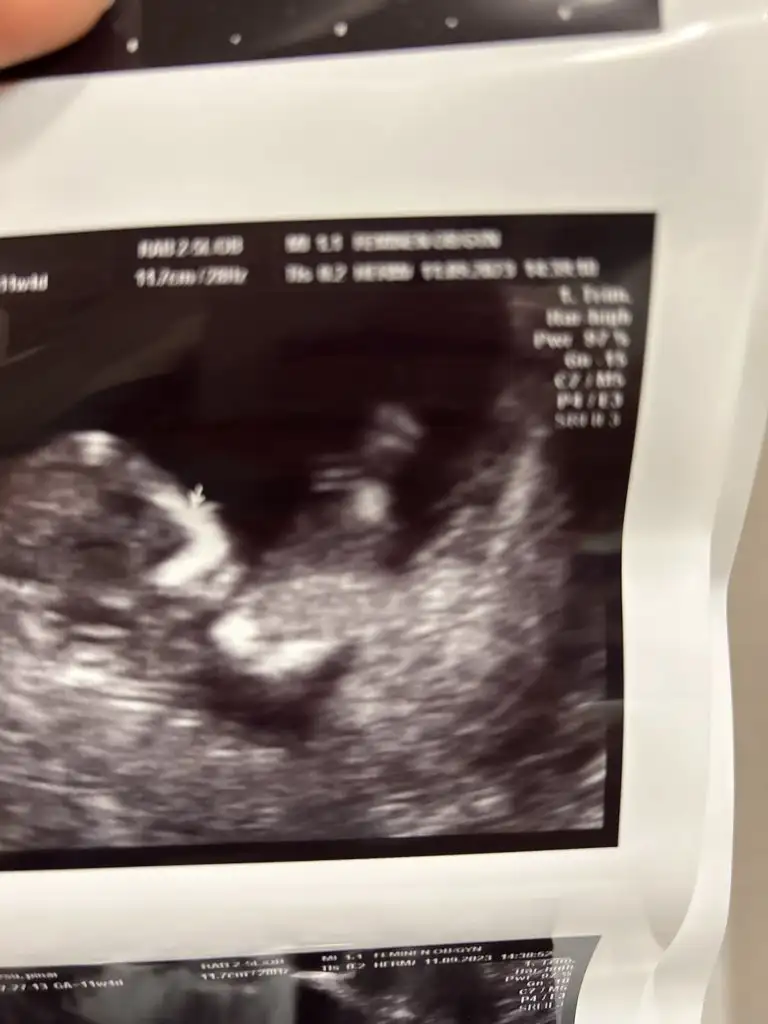

Erkeklerin direk belli oluyor ya hiç bidaha ki ay tekrar bakalım muhabbeti yok benim iki oglumdada hemen öğrendik hatta ikinci oğlum 11+1 de belli oldu ama bu minnaka 13+1 de perinatolog bile net bişey diyemedi %70 kız %30 yanılma payı birakiyorum dedi bekle şimdi 3 hafta dahaBenimki bu gün pipini gösterdi![]()

Yok kuzum benimki 12+2 haftada göstermedi ama fetal DNA öğrendik..bu günde 14+6 öyle gördük zaten artık biliyordukErkeklerin direk belli oluyor ya hiç bidaha ki ay tekrar bakalım muhabbeti yok benim iki oglumdada hemen öğrendik hatta ikinci oğlum 11+1 de belli oldu ama bu minnaka 13+1 de perinatolog bile net bişey diyemedi %70 kız %30 yanılma payı birakiyorum dedi bekle şimdi 3 hafta daha![]()

15+2 ya da 3Kaç haftalık oluyorsunuz o zamann![]()

E bnımkıde 11+3 te başı öne eğiktiPozisyon şubaşı öne eğik olunca sanırım kız olur demek istedi. Bizimkinin ayakları havada

oyyy minnoş el sallıyor snakiE bnımkıde 11+3 te başı öne eğikti

Bugunde baş aşagı idi

Doktor birden renkli ultrasonu açtı

Arkası dönüktü ellerıyle yuzunu kapamıştı